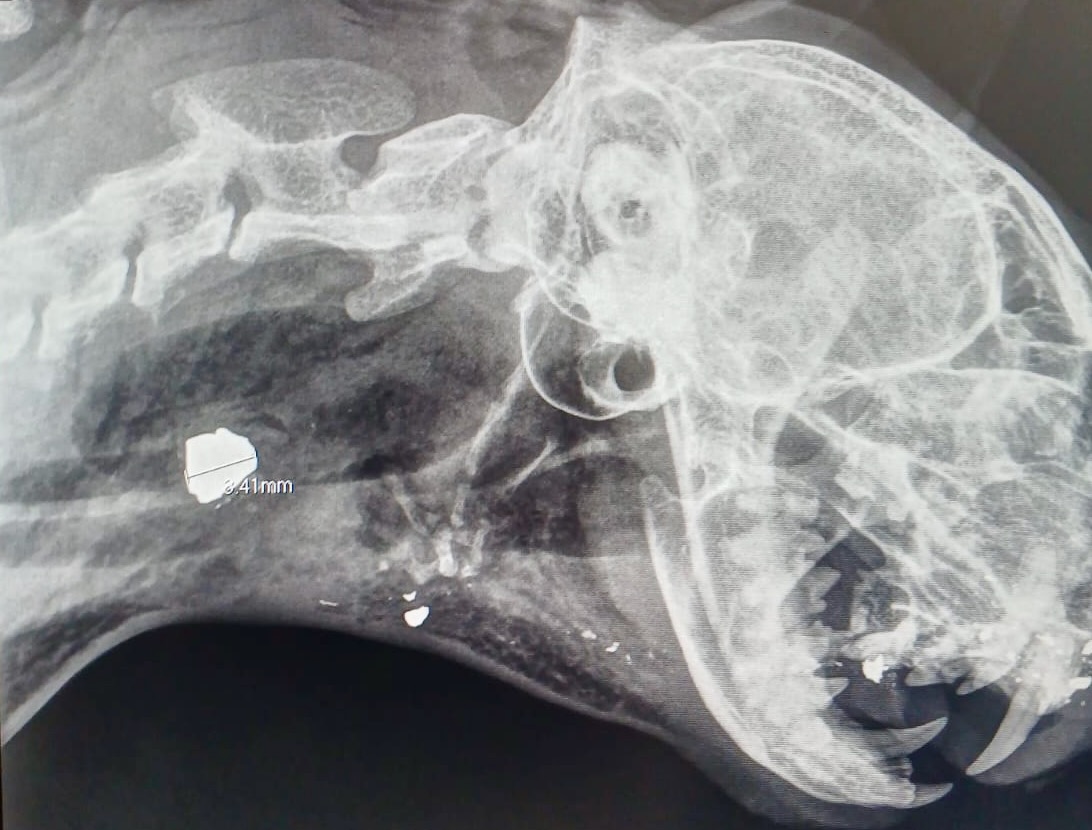

Das sind Artikel, die man nicht so gerne schreibt, die aber auch eine Warnung sind: In Wendorf bei Möllenhagen ist Mitte Juli die Katze „Susi“ abends blutend nach Hause gekommen. Der Tierarzt zeigte der Besitzerin dann voller Entsetzen das Röntgenbild. Der Katze wurde offenbar aus nächster Nähe ins Gesicht geschossen. „Es ist für mich unvorstellbar, dass es Menschen gibt, die so brutal und ohne jeglichen Gefühle sind. Und wer weiß, was diese charakterschwachen Typen als nächstes vorhaben“, schreibt die Besitzerin der Katze an „Wir sind Müritzer“. Deswegen will sie das Geschehen öffentlich machen. Zum Glück geht es „Susi „wieder gut. Der Tierarzt aus Neustrelitz hat ganze Arbeit geleistet und das Geschoss mit sehr viel Können entfernt. Dafür sind die Besitzer überaus dankbar. „Es ist nicht nur ein Tier, es ist ein Herz, das schlägt, eine Seele die fühlt und ein Leben das leben will“, so die betroffenen Besitzer.